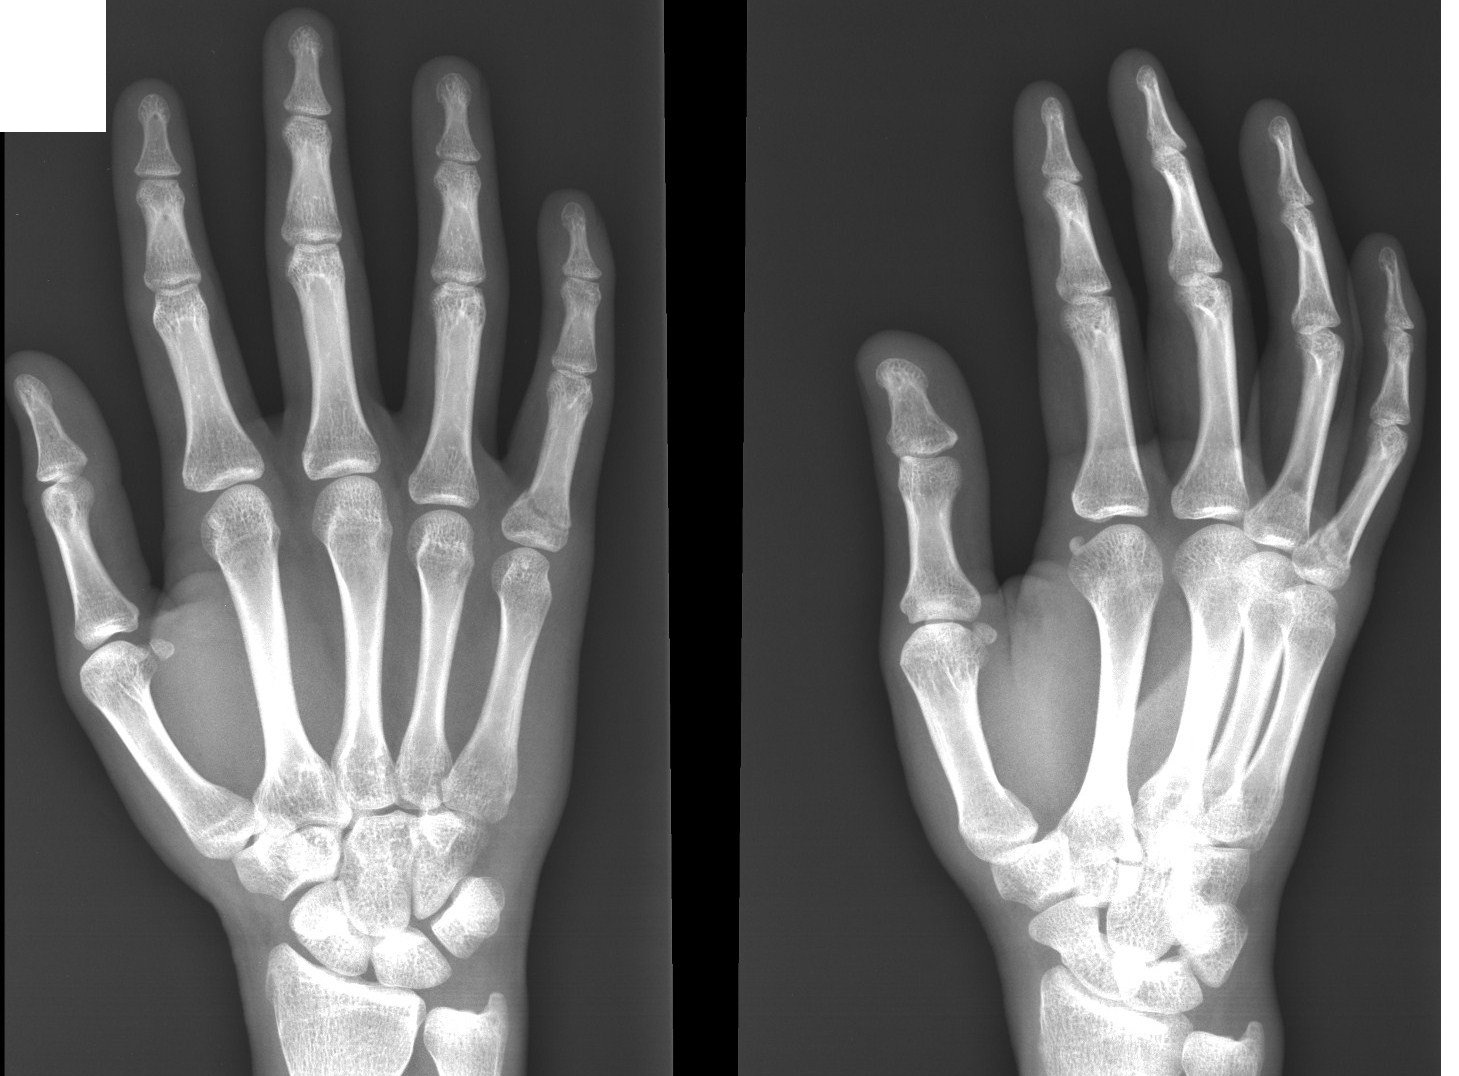

Подборка рентгеновских снимков лучезапястного сустава

Раздел: Объективный взгляд